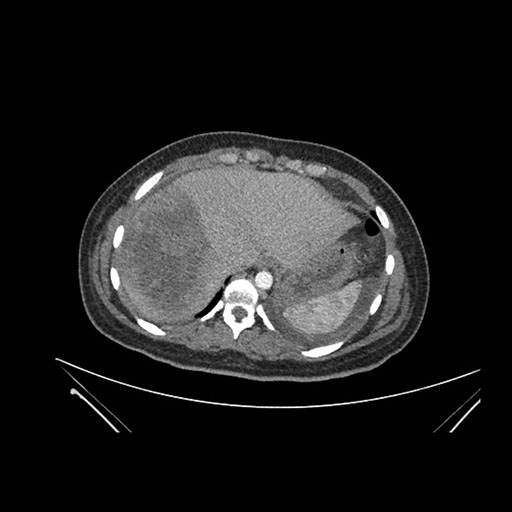

Vasculobiliary injury [M28]

Imaging Analysis

Look through the patient's CT scan to identify any areas of concern for the necessary procedure.

Axial Arterial

Axial Venous